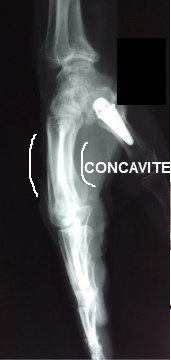

Salut, svp je ne comprends pas trop cette phrase: "On parle de région palmaire lorsque les métacarpiens forment une concavité antérieure" :( prriez-vous ajouter un schéma pr que je puisse bien visualiser svp).

Cette concavité antérieure tu peux la voir sur la paume de ta main, car tu peux ressenti un creux au centre de ta paume.

Je t'ai mise une image radiologique pour que tu puisses visualiser :

metacarpe.jpg (11.19 Kio) Vu 199 fois

Dis moi si ça t'aide :wink2: